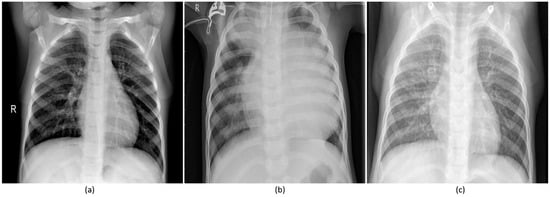

Figure 1.

Pediatric CXRs: (a) Normal CXR showing clear lungs with no abnormal opacification; (b) Bacterial pneumonia exhibiting focal lobar consolidation in the right upper lobe; (c) Viral pneumonia manifesting with diffuse interstitial patterns in both lungs.